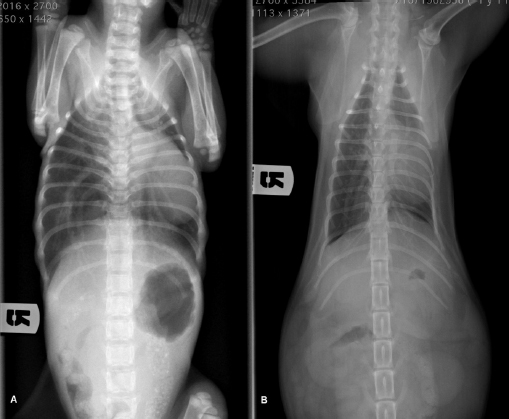

Radiographic examination revealed severe dorsal displacement from the fifth sternebra to the xiphoid cartilage and a dorsal displacement of the cardiac silhouette on the lateral view (Fig. 1A), and a left mediastinal shift and compression of the left pulmonary lobes on the ventrodorsal view (Fig. 2A). VI and FSI were measured on the radiographs, being 3.2 and 9.1, respectively. The authors decided to measure these two indices also at the level of T9 because this vertebra corresponded to the point of minimum height of the thorax. VI and FSI at the level of T9 were 2.3 and 15.2, respectively. The authors measured also the minimum thoracic height (MinTH) that resulted 4.3 mm, at the level of the last sternebra.

Fig. 1. Left lateral radiographic view of the thorax of the cat with pectus excavatum. Comparison of patient’s thorax before (A) and after (B) surgical treatment at 9 months postoperatively.

Fig. 2. Ventrodorsal radiographic view of the thorax of the cat with pectus excavatum. Comparison of patient’s thorax before (A) and after (B) surgical treatment at 9 months postoperatively.

Radiographs were obtained as previously described at each follow-up examination (Figs. 1B and 2B). IV, FSI, and MinTH were calculated and the values are reported in Table 1.

Nine months postoperatively the cat underwent an ovariohysterectomy with no anesthetic-related complications. The cat was discharged from hospital 6 hours postoperatively and recovered uneventfully. Radiographs were obtained as previously described before the surgery. VI and FSI resulted in 12.4 and 1.5, respectively; the same indexes measured at the level of T9 were 9.4 and 2.1, respectively, and MinTH was 26 mm.